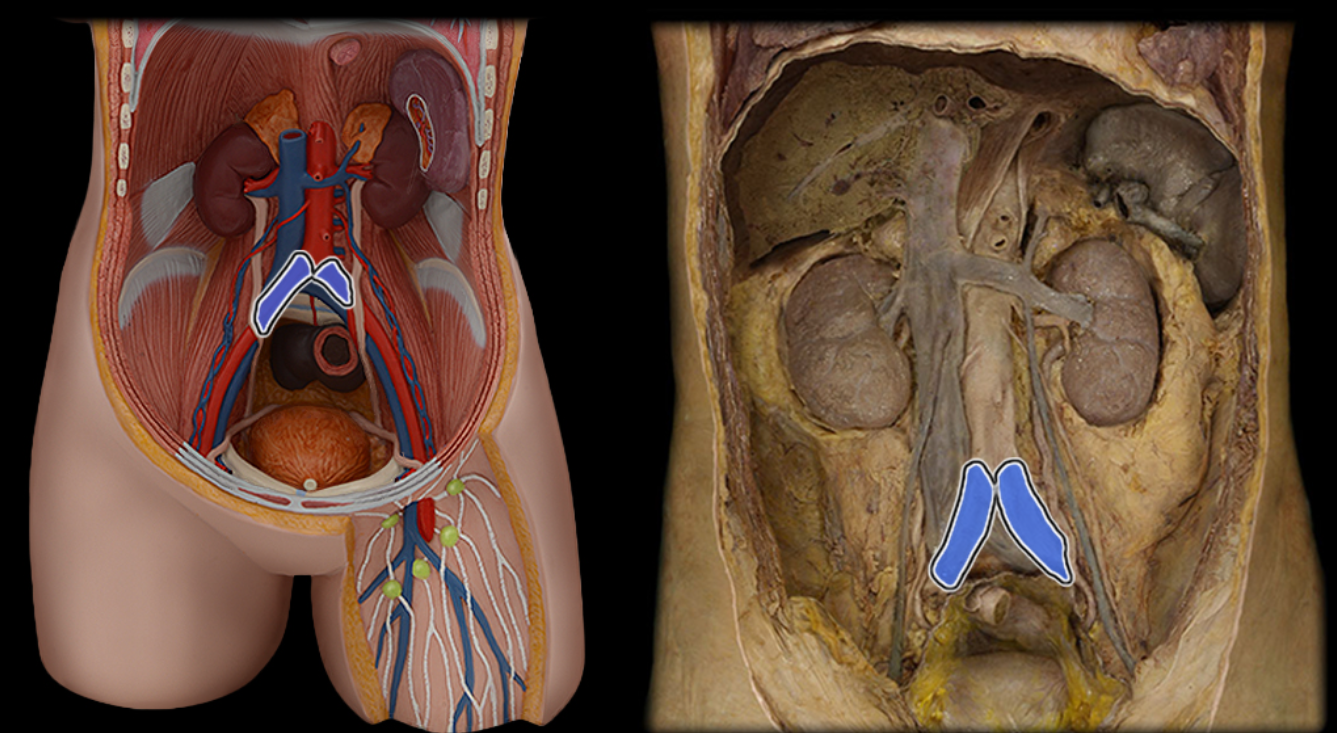

Abdominal aorta

Common iliac a.

Common iliac v.

External iliac a.

External iliac v.

Inferior vena cava

Renal a.

Renal v.

Superior mesenteric a.